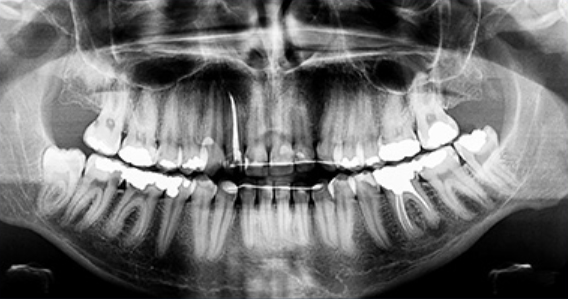

매복된 사랑니는 3D 첨단 CT촬영으로 상태를 정밀검사하고 발치계획을 세웁니다.

사랑니 발치 시에는 뿌리가 신경관과 근접해 있는지 또 어느쪽으로 휘어져 있는지를

파악해야

훨씬 더 안전하고 편하게 또 빠르게 뽑을 수 있습니다.

최첨단 3차원 CT를 이용하여 사랑니 뿌리의 위치와

신경관 위치 등을 정밀하게 분석한 후 시행하고 있습니다.